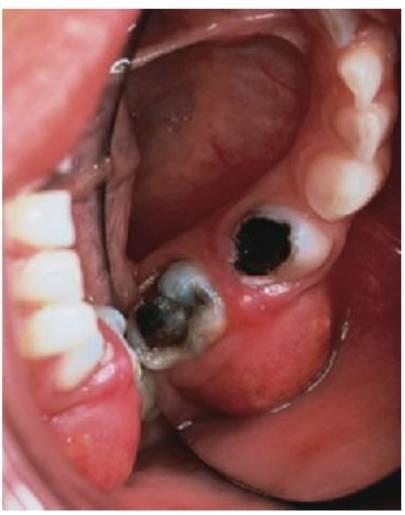

Eliminación de la caries

El diente tratado debe quedar completamente exento de caries antes de llevar a cabo una pulpotomía. La recomendación de eliminar caries desde la periferia a la pulpa no sólo previene la contaminación con restos cariosos del lugar de la pulpotomía sino que también reduce el riesgo de exposición pulpar inadvertida. El acceso a la pulpa coronal requiere una eliminación completa del techo de la cámara pulpar. La amputación de la pulpa coronal requiere un corte limpio en el área del suelo pulpar. Las interdigitaciones residuales de tejido en el lugar de amputación crearán problemas con la hemostasia. La instrumentación rotatoria a alta velocidad con copiosa irrigación de agua en spray favorece el corte óptimo. Si se perfora el suelo de la cámara pulpar, habrá que extraer el diente.

Hemostasia

Debe obtenerse hemostasia en el lugar de la pulpotomía antes de aplicar el agente terapéutico y este efecto se consigue con una irrigación continua y frotando suavemente con bolitas de algodón. Debe producirse en 5 minutos y si no se puede detener la hemorragia, se considera que la inflamación pulpar se ha extendido a las raíces y está asociada a un mal pronóstico que se denomina «signo de sangrado». En estos casos, deben considerarse la pulpectomía o la extracción.